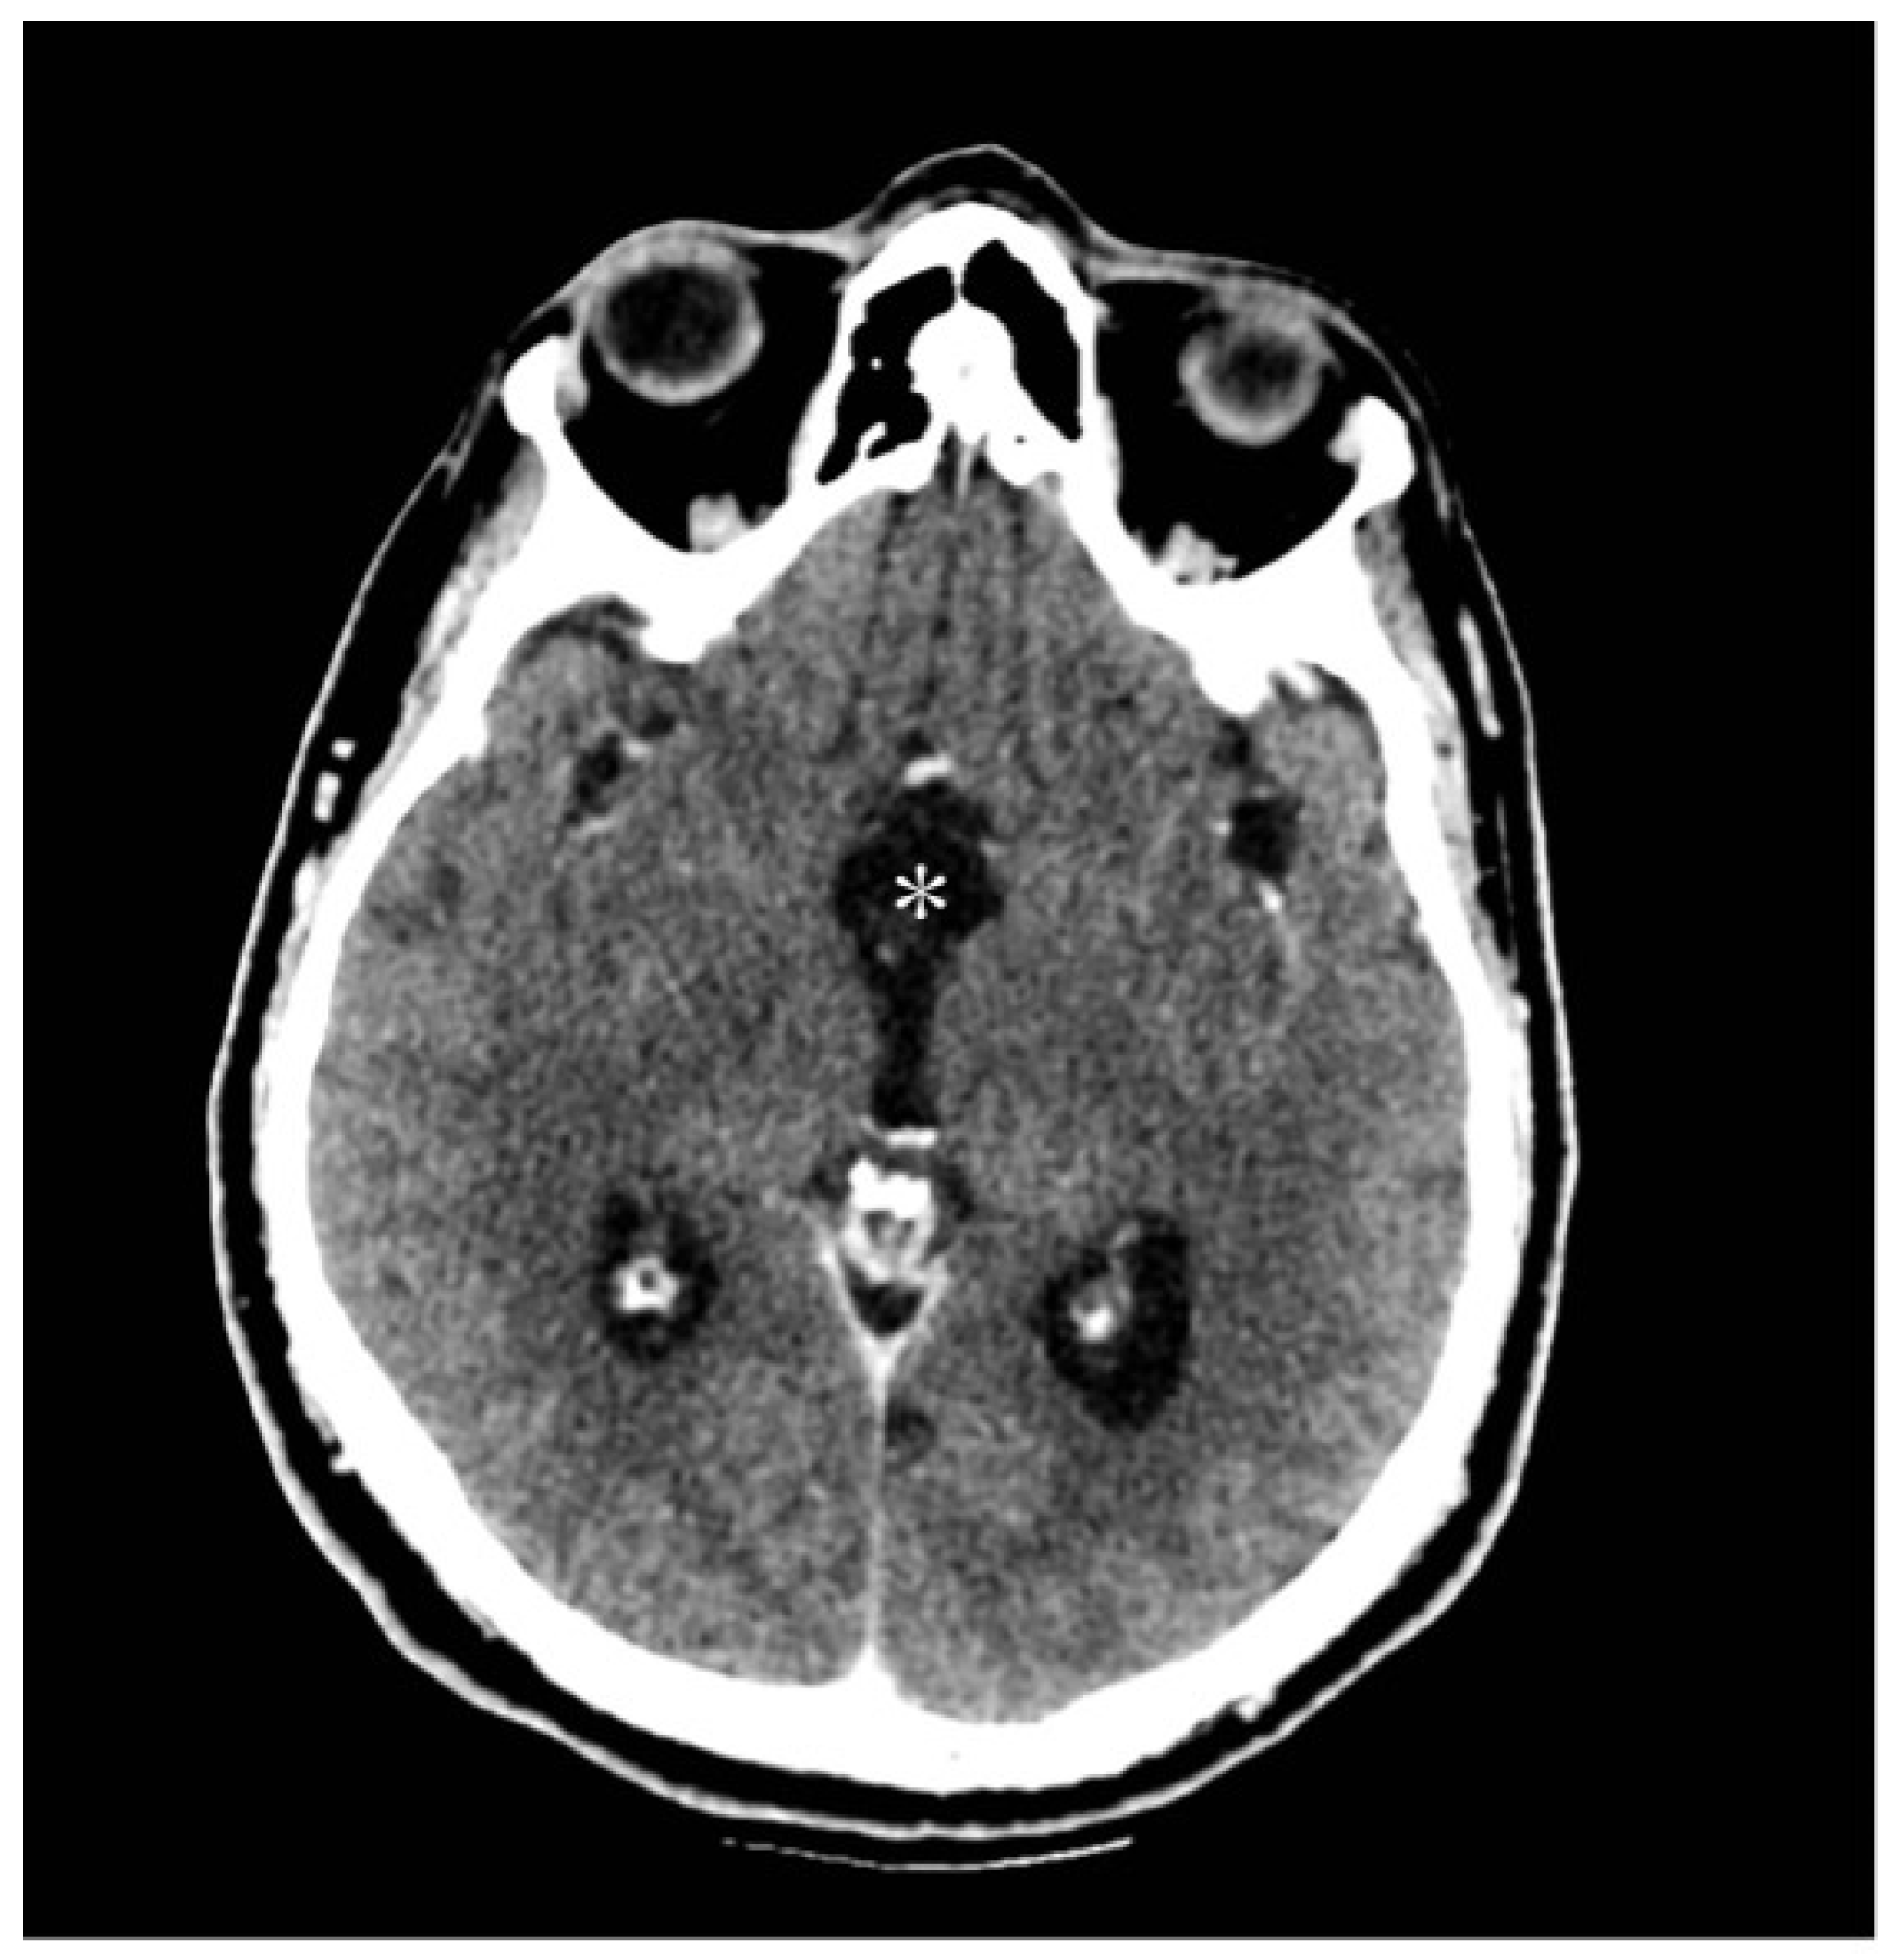

The patient underwent neurosurgical resection via a right parasagittal craniotomy and interhemispheric transcallosal approach. The lesion, identified as a medial protrusion beneath the septum pellucidum, was encapsulated, brownish, and vascularized. A gross-total resection was performed (Figure 7A,B) and subsequently confirmed by a postoperative CT scan (Figure 8).

Figure 8.

Postoperative CT brain scan showing a gross total resection (white asterisk) of the lesion with an initial decrease in ventricular size.